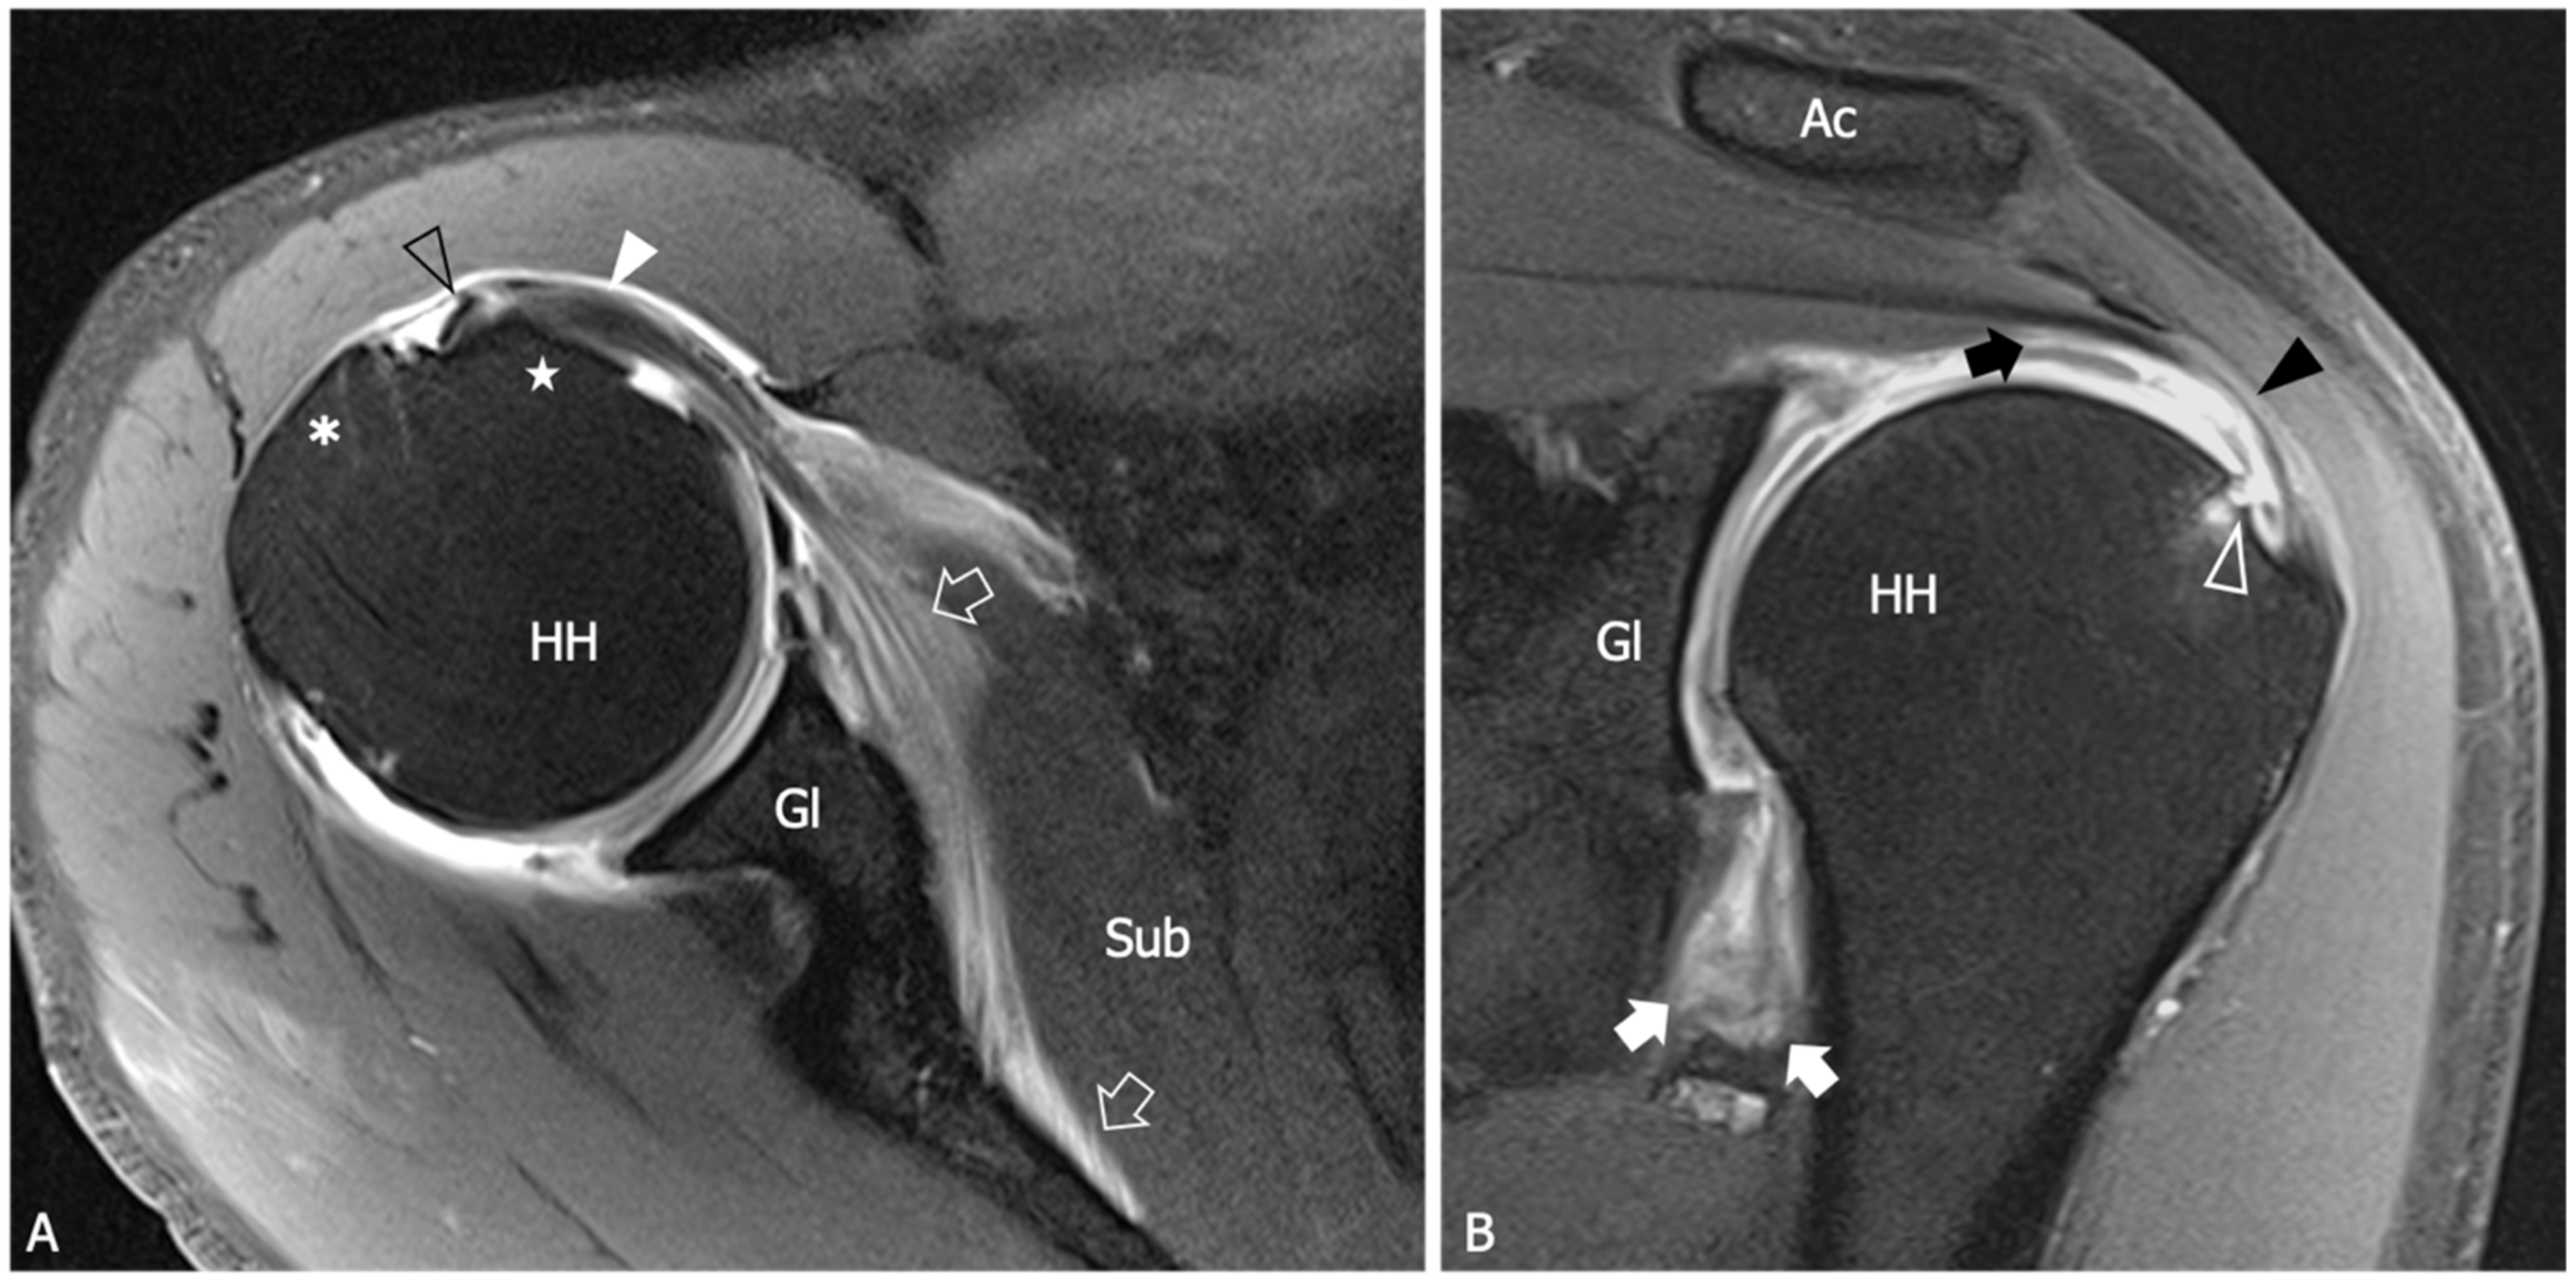

| Thickening of the coracohumeral ligament, fat obliteration of the rotator interval, hyperintensity and thickening of the inferior glenohumeral ligament, and contrast enhancement of the axillary joint capsule and the rotator interval are the most accurate signs of AC. The sensitivity and specificity of inferior glenohumeral thickening detected on conventional MRI are not significantly different from those detected on direct MR Arthrogram: consequently, the non-arthrogram MRI is recommended for AC diagnosis. | [53] |

| The rotator interval capsule thickness ≥7 mm has a specificity of 86% and a sensitivity of 64% for AC diagnosis. A coracohumeral ligament thickness ≥4 mm has high specificity (95%) but lower sensitivity (59%) for AC. Obliteration of the triangular fat pad inferior to the coracohumeral ligament has high specificity (100%) and poor sensitivity (32%). | [54] |

| Thickening of the rotator interval over 6 mm on sagittal oblique proton-density images may correlate with the patient’s range of rotational motion. An axillary recess capsule thickness of more than 4.5 mm measured on T1 oblique coronal images demonstrated the greatest diagnostic accuracy for AC diagnosis, with a sensitivity, specificity, and overall accuracy of 91%, 90%, and 90%, respectively. | [55] |

| Obliteration of the subcoracoid fat triangle has been more frequently observed in early stages of AC. Capsule thickness and hyperintensity on proton density sequence correlate with clinical stages. | [56] |

| Hyperintensity in the axillary pouch/inferior glenohumeral ligament complex on MRI using non-arthrography T2-weighted fat-suppressed sequences demonstrated high sensitivity (85.3–88.2%) and specificity (88.2%) and low variability among different observers with a kappa value of 0.85. | [57] |

| An axillary recess capsule thicker than 4 mm on T1 oblique coronal MR images suggests a diagnosis of AC with a sensitivity of 70% and a specificity of 95%. | [58] |

| A positive linear correlation is demonstrated between the grade of axillary recess capsule enhancement, the thickness of the joint capsule, and the intensity of pain in individuals with AC. No association was observed between the aforementioned parameters and the severity of range of motion limitation. | [59] |

| No differences in the accuracy of AC diagnosis emerged between conventional MRI and gadolinium-enhanced MRI despite the intravenous administration of contrast agent demonstrated to have some effects in increasing the reader’s confidence in measuring the joint capsule. | [60] |